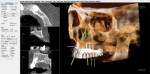

Figure 3 illustrates the CT diagnosis and proper positioning of six maxillary dental implants within the viability of the existing anatomy using software (Invivo 5, Anatomage Dental, www.anatomage.com). Implants (3.7-mm diameter Glidewell Inclusive tapered implants) were strategically placed essentially parallel and away from the sinus areas in the edentulous maxilla as determined by CT planning. A surgical guide was created to allow for initial depth determination. Subsequent increase in diameter of the surgical burs created the osteotomy site for the implants. For this patient, implants were positioned in the edentulous areas of position Nos. 4 through 6 and 11 through 13. They were torqued to 25 Ncm, flat cover screws were placed, and the existing maxillary conventional complete denture was seated. A Mucopren® Soft liner (Kettenbach, www.kettenbach.com) was used to condition the tissue during the 4-month integration period.